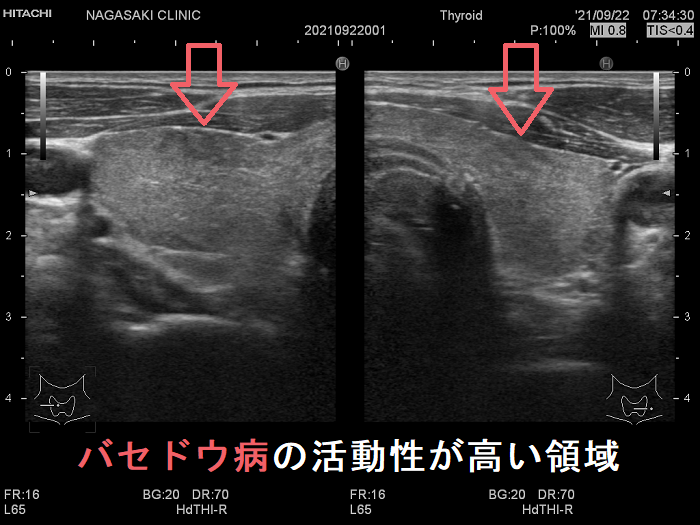

局所的に血流が多く、低エコーな領域

抗甲状腺薬投与により、甲状腺機能が正常に保たれているバセドウ病では、治療前の”火炎状血流増加”と呼ばれる甲状腺内部の異常血流増加が減少していきます。しかし、局所的に血流が多く、低エコーな領域は活動性が残存しています。(J Clin Ultrasound. 2005 Oct;33(8):381-5. doi: 10.1002/jcu.20157.)(Exp Clin Endocrinol Diabetes. 2013 Jan;121(1):1-5.)(AJR Am J Roentgenol. 1996 Jan;166(1):203-7.)

局所的に血流が多く、低エコーでバセドウ病の活動性が高い領域

局所的に血流が多く、低エコーでバセドウ病の活動性が高い領域  ドプラーモード